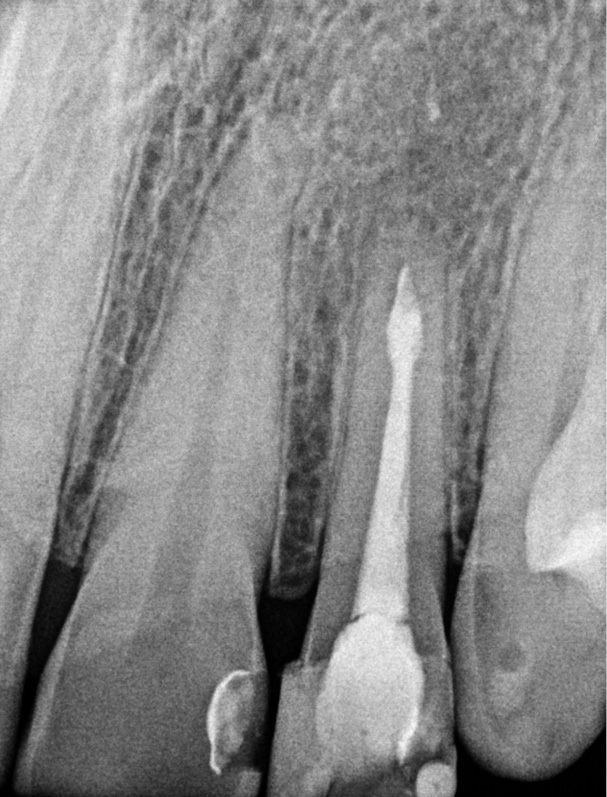

Title: Endodontic and surgical treatment of a lateral maxillary incisor with internal type B resorption

Streszczenie: W pracy opisano leczenie endodontyczno-chirurgiczne 34-letniej pacjentki, u której rozpoznano torbiel korzeniową szczęki. Torbiel zębopochodną wyłuszczono po uprzednim leczeniu endodontycznym przyczynowego zęba 22 z resorpcją wewnętrzną typu B. Na podstawie zdjęć kontrolnych wykonanych po 3, 12 i 24 miesiącach od zakończenia leczenia można stwierdzić, że rokowanie dotyczące leczenia zęba jest pomyślne.

Summary: The paper presents a case of the endodontic and surgical treatment of a periapical radicular cyst in a 34-year-old patient.

The odontogenic cyst was removed by curettage after the root canal treatment of the tooth with internal type B resorption. On the basis of the checkup radiographs taken after 3, 12 and 24 months, it is possible to conclude that the prognosis for the survival of the tooth is good.